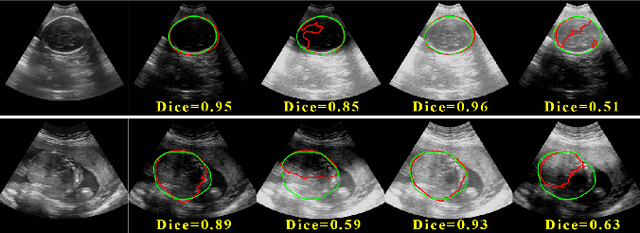

Abstract:Deep segmentation models that generalize to images with unknown appearance are important for real-world medical image analysis. Retraining models leads to high latency and complex pipelines, which are impractical in clinical settings. The situation becomes more severe for ultrasound image analysis because of their large appearance shifts. In this paper, we propose a novel method for robust segmentation under unknown appearance shifts. Our contribution is three-fold. First, we advance a one-stage plug-and-play solution by embedding hierarchical style transfer units into a segmentation architecture. Our solution can remove appearance shifts and perform segmentation simultaneously. Second, we adopt Dynamic Instance Normalization to conduct precise and dynamic style transfer in a learnable manner, rather than previously fixed style normalization. Third, our solution is fast and lightweight for routine clinical adoption. Given 400*400 image input, our solution only needs an additional 0.2ms and 1.92M FLOPs to handle appearance shifts compared to the baseline pipeline. Extensive experiments are conducted on a large dataset from three vendors demonstrate our proposed method enhances the robustness of deep segmentation models.

Abstract:Deep Neural Networks (DNNs) suffer from the performance degradation when image appearance shift occurs, especially in ultrasound (US) image segmentation. In this paper, we propose a novel and intuitive framework to remove the appearance shift, and hence improve the generalization ability of DNNs. Our work has three highlights. First, we follow the spirit of universal style transfer to remove appearance shifts, which was not explored before for US images. Without sacrificing image structure details, it enables the arbitrary style-content transfer. Second, accelerated with Adaptive Instance Normalization block, our framework achieved real-time speed required in the clinical US scanning. Third, an efficient and effective style image selection strategy is proposed to ensure the target-style US image and testing content US image properly match each other. Experiments on two large US datasets demonstrate that our methods are superior to state-of-the-art methods on making DNNs robust against various appearance shifts.